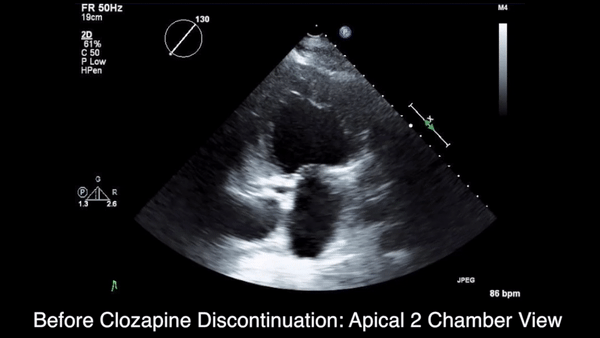

More than 4 years after the initiation of clozapine and after various treatments for multiple symptoms (Sidebar), the patient was diagnosed with heart failure (HF) with a reduced ejection fraction (EF) of 10% to 15%. She was referred to the cardiology HF clinic. Her dose of clozapine 150 mg at bedtime was discontinued after a discussion with psychiatry. She had a negative workup for other HF etiologies and was started on HF medications that included carvedilol, losartan, and spironolactone. After discontinuation of clozapine, her psychiatric symptoms worsened, and she was admitted to the psychiatry unit twice within a year. Two months after clozapine was discontinued, a repeat echocardiogram (ECHO) was obtained and was essentially unchanged. A chest X-ray (CXR) obtained 4 months after clozapine discontinuation demonstrated a normalized cardio-mediastinal silhouette. A third ECHO was ordered during her second psychiatric admission, which was 11 months after clozapine discontinuation; this revealed an improved left ventricular EF (LVEF) of 30% to 35% and resolution of left ventricular (LV) dilation.

This patient’s clinical course led to an extensive chart review that investigated whether there may have been earlier signs and symptoms of HF or cardiomyopathy. It was discovered that the initial HF signs and symptoms were likely present for about 1 year before the diagnosis was made and after having been on clozapine for about 40 months (Patient’s ECHO before and after clozapine discontinuation, click here for additional ECHO perspectives ).